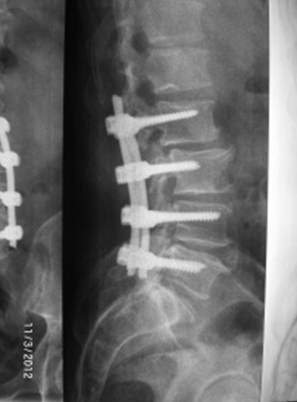

Ողնաշարային խողովակի ստենոզի (նեղացման) ժամանակ ողնուղեղն ազատելու նպատակով հեռացվում են ողերի հետին տարրերը և, ինչպես նրանց անկայունության ժամանակ, իրականացվում է ողնաշարի տրանսպեդիկուլյար ամրացում:

|

Ողնաշարի գոտկային հատվածի ողերի անկայունություն և ողնաշարային խողովակի ստենոզ |

Վիրահատական շտկումից առաջ Վիրահատական շտկումից հետո